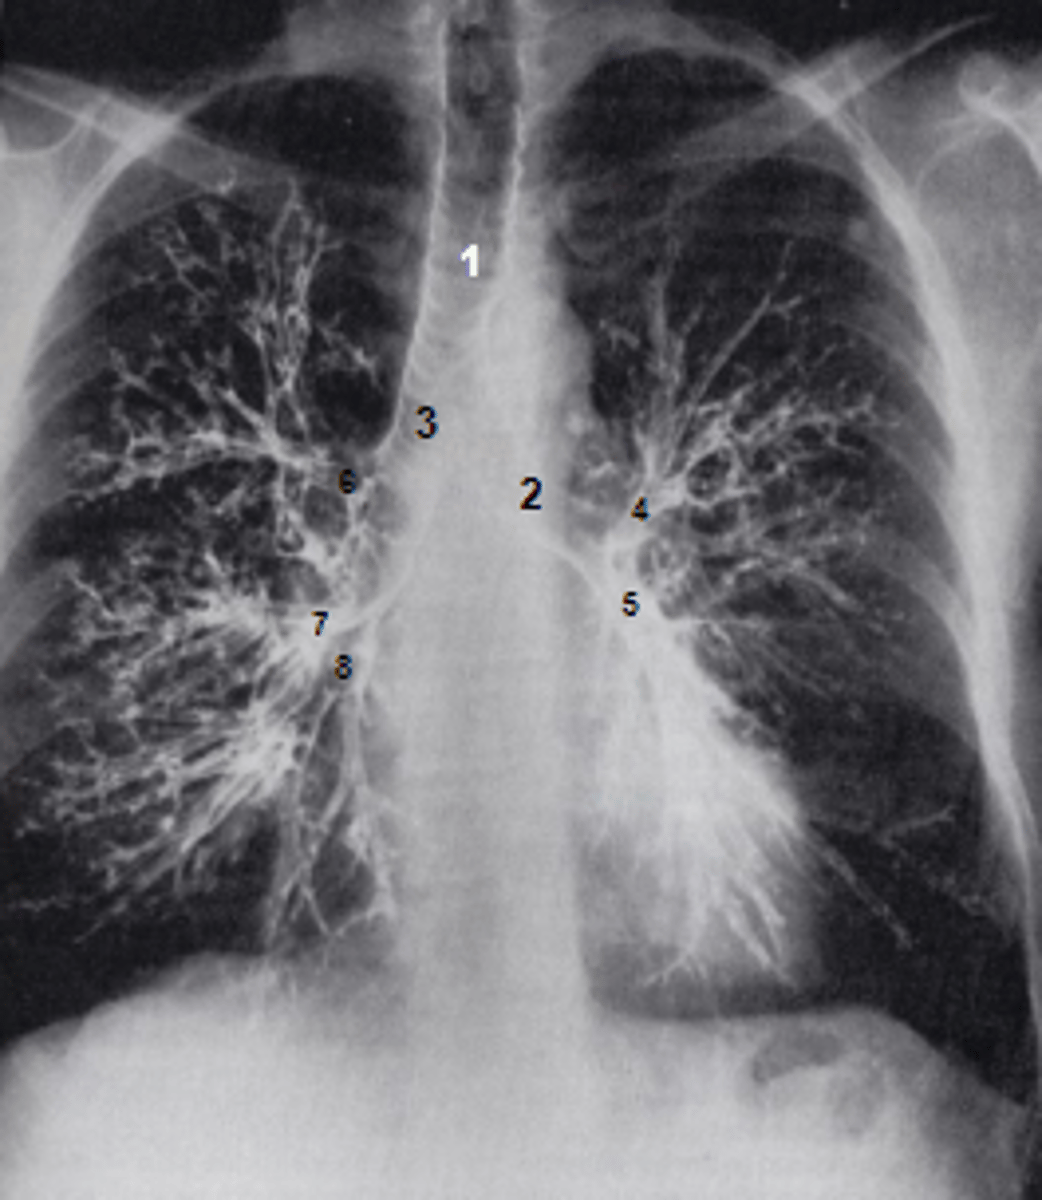

1

at what number is the trachea

2

at what number is the left main bronchus

3

at what number is the right main bronchus

4

at what number is the left superior lobar bronchus

5

at what number is the left inferior lobar bronchus

6

at what number is the right superior lobar bronchus

7

at what number is the right middle lobar bronchus

8

at what number is the right inferior lobar bronchus